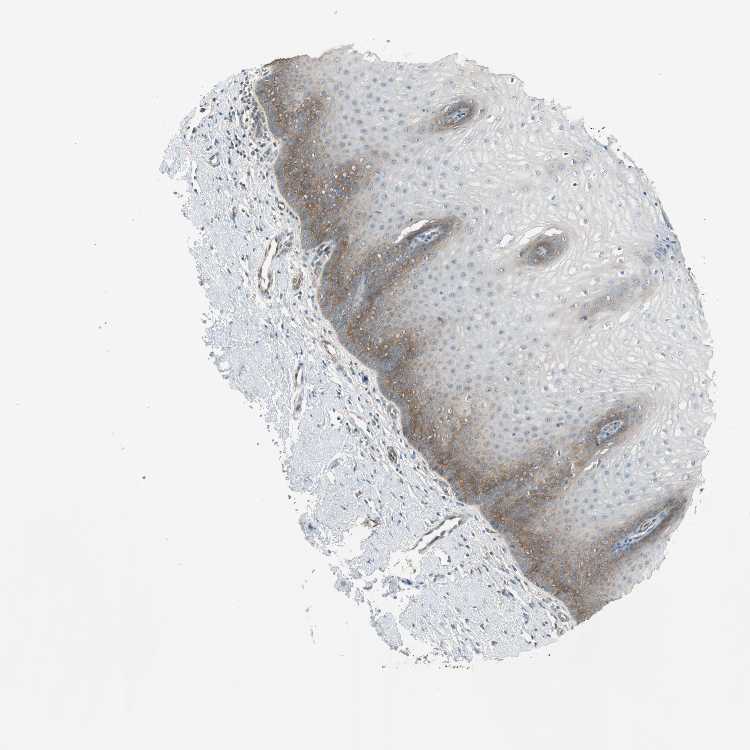

CERVIX - Antibody stainingi

Antibody staining in the annotated cell types in the current human tissue is reported as not detected, low, medium, or high, based on conventional immunohistochemistry profiling in selected tissues. This score is based on the combination of the staining intensity and fraction of stained cells.

Each image is clickable and will lead to virtual microscopy that enables deeper exploration of all samples and also displays staining intensity scores, fraction scores and subcellular localization as well as patient and tissue information for each sample.

Antibody HPA040983Antibody HPA056548Antibody CAB009110

Glandular cells MediumLowLow

Squamous epithelial cells -LowNot detected